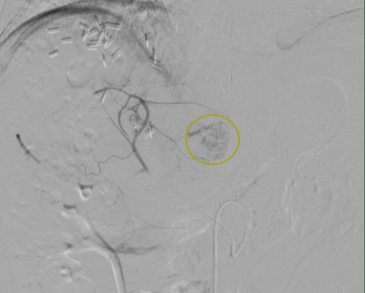

发现本次复发肿瘤病灶位于肝尾状叶

其位置位于腹腔深部

且后方为腹主动脉这一人体重要血管

决定为王先生先行动脉介入化疗栓塞

治疗病灶的同时标记病灶

肝尾状叶肿瘤病灶